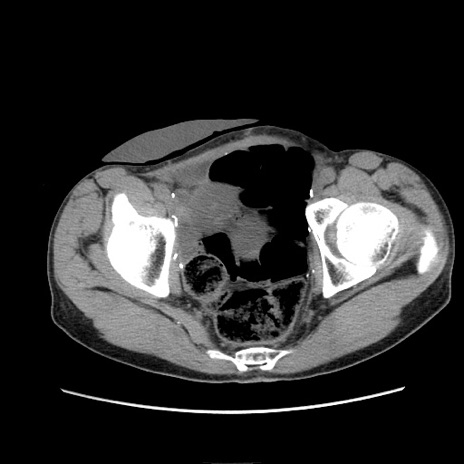

症例11(横断像)

【症例】 60歳代男性

【主訴】 下腹部痛

【現病歴】 本日夜中より下腹部痛の症状認め、受診。

【既往歴】 膀胱癌(膀胱全摘+尿管皮膚瘻術) 、胃癌術後

【身体所見】 BT 35.3℃、PR 58/min、BP 136/98mHg、腹部平坦、軟、腸蠕動音±、ストマ留置あり、左上腹部~正中部に圧痛あり、反跳痛なし。

【データ】WBC 5100、CRP0.01